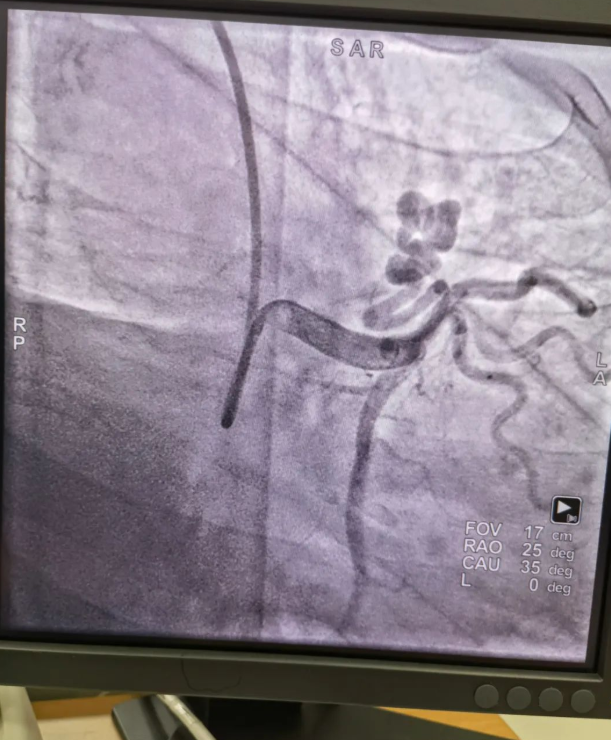

不久前,來自新疆的患者石先生去年至今反復(fù)胸悶、氣短、胸痛,就診于新疆某院,懷疑“冠心病”,住院行冠狀動脈造影術(shù),石先生造影提示“冠狀動脈肺動脈瘺”,而他并非“冠心病”,所以給予的“冠心病”治療,效果不佳。出院后仍反復(fù)出現(xiàn)胸痛、胸悶、氣短等癥狀,經(jīng)親友介紹了解到西安國際醫(yī)學(xué)中心醫(yī)院心臟病醫(yī)院心臟內(nèi)科二病區(qū)曾廣偉主任,多年來潛心研究心臟病介入治療,成功主刀救治了許許多多高危復(fù)雜病例,尤其是在先心病及結(jié)構(gòu)性心臟病封堵,以及冠心病、心律失常射頻消融及起搏治療等方面積累了豐富的診療經(jīng)驗。

此病例罕見,在曾廣偉從醫(yī)18年生涯里曾碰到有2個印象深刻的病例,患者分別是53歲和66歲,當(dāng)時建議患者入院進行動脈瘺的封堵術(shù),但患者和家屬考慮到這個手術(shù)案例極少,風(fēng)險也高,均未接受手術(shù)治療建議,只是能采取藥物保守治療,出院后隨訪得知患者癥狀緩解效果不佳,后來在隨訪中也與53歲患者失去了聯(lián)系,而66歲患者因冠狀動脈肺動脈瘺出現(xiàn)反復(fù)心衰,在當(dāng)?shù)蒯t(yī)院藥物治療,短短2年時間,患者因為動脈瘺未及時手術(shù)失去了生命。所以此次患者石先生到訪,曾廣偉主任在詳細(xì)掌握病例資料基礎(chǔ)上,果斷建議進行動脈瘺的封堵術(shù)治療,為了提高手術(shù)成功率和精準(zhǔn)度,曾廣偉主任搜集相關(guān)診療資料,反復(fù)推演論證,經(jīng)過相當(dāng)充足的準(zhǔn)備工作,于5月18日成功進行了封堵手術(shù),完全堵上了瘺口。

患者術(shù)后第2天,已經(jīng)沒有明顯的胸悶、氣短、胸痛等癥狀,目前身體狀態(tài)良好。本次手術(shù)曾廣偉主任及其團隊,采取從右手臂一根血管進入,并在2小時之內(nèi)完美封堵,創(chuàng)口小,痛苦小。手術(shù)雖然難度大、風(fēng)險高,相關(guān)案例也少,但是曾廣偉主任主刀即在巔峰,這樣一臺完美的手術(shù)靠的不是運氣,是豐富的臨床手術(shù)經(jīng)驗,扎實的專業(yè)知識儲備,以及對醫(yī)療事業(yè)的孜孜追求。

冠狀動脈瘺是指冠狀動脈與心腔、冠狀靜脈、肺動脈等的異常連接,是一種少見的先天性心臟病,發(fā)病率為1.3%。而冠狀動脈肺動脈瘺是冠狀動脈與肺動脈之間產(chǎn)生的一種血管性瘺口,導(dǎo)致冠狀動脈里的血液流入肺動脈里,使冠狀動脈里血液流量減少,出現(xiàn)心肌供血不足,冠狀動脈肺動脈瘺會使患者出現(xiàn)胸部疼痛、胸悶、呼吸困難、頭暈、乏力等一系列癥狀,隨著疾病不斷進展,可引發(fā)心功能的障礙和心肌缺血,肺動脈會逐漸形成肺動脈高壓,還可能導(dǎo)致動脈瘤的破裂,甚至威脅病人的生命安全,所以早期發(fā)現(xiàn)和治療冠狀動脈肺動脈瘺,對病人的預(yù)后改善具有重要的意義。